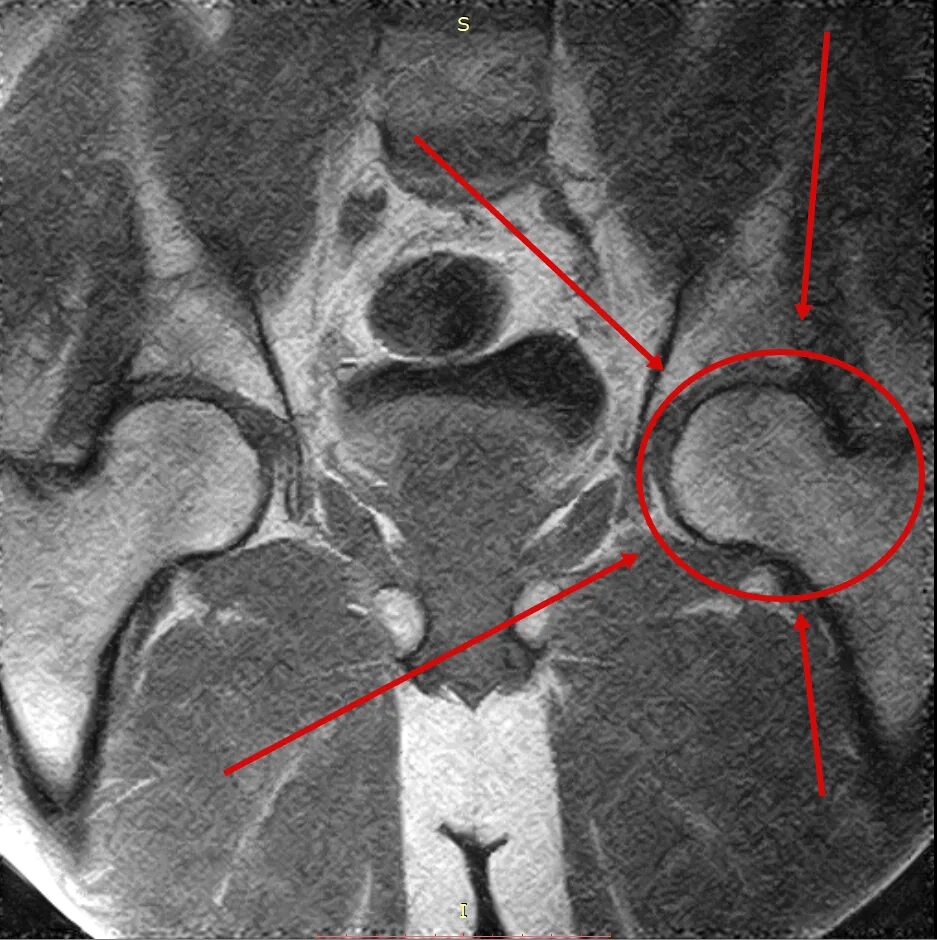

Некроз головки по мкб